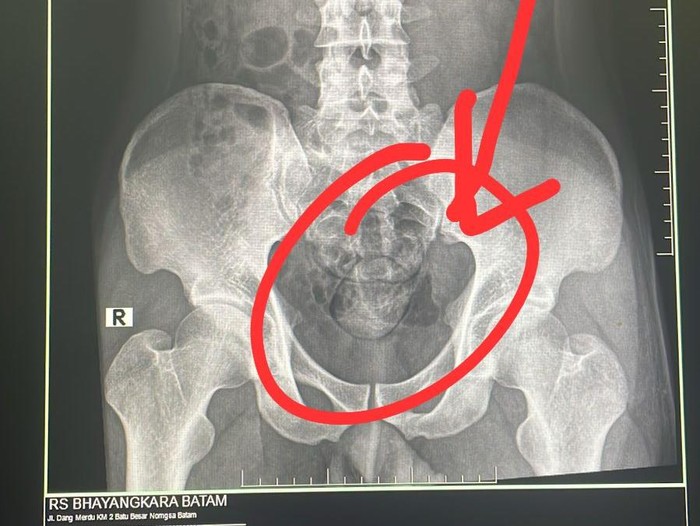

Barang bukti narkoba yang disimpan tersangka di dalam anus (Foto: Polda Kepri) |

Pelaku kemudian dibawa anggota Subdit 2 Ditresnarkoba Polda Kepri ke RS Bhayangkara untuk dilakukan rontgen di bagian radiologi.

"Hasil dari rontgen ditemukan dua buah kapsul di dalam perut. Selanjutnya pelaku mengeluarkan dua kapsul tersebut di toilet RS Bhayangkara. Total berat narkoba jenis sabu sebanyak 100 gram," ujarnya.